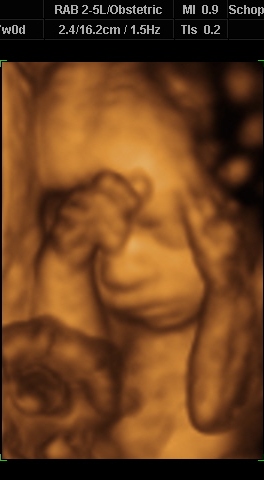

Ugye most vagyok a 29. hét elején. Babuba 1700 (!)

gramm, a doki azt mondta, gyönyörűen fejlődik, egészséges, minden oké.

A 32 hetes babák vannak 1600 gramm körül.

Egyébként végig aludt, 1x-2x kinyitotta a szájacskáját, meg mosolygott. Forgolódtam az oldalamra, vissza, doki bökdöste a hasamat, de őt semmi nem érdekelte. Lehet, azért van kicsit lebiggyesztett szájtartása a fotón, mert azt akarta mondani: Haggyatok má békéééén!